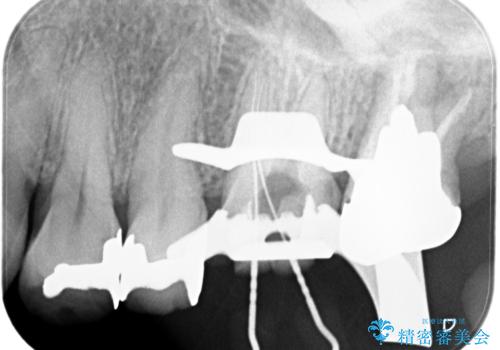

最後方臼歯は根尖部まで歯周病が進行しており、抜歯を行なったのち、残存歯は歯周外科を行なったのちオールセラミッククラウンにて修復治療を行なっています。

歯周外科を行う事により歯周ポケットを除去し予知性の高い治療を行うことができますが治療期間がかかります。